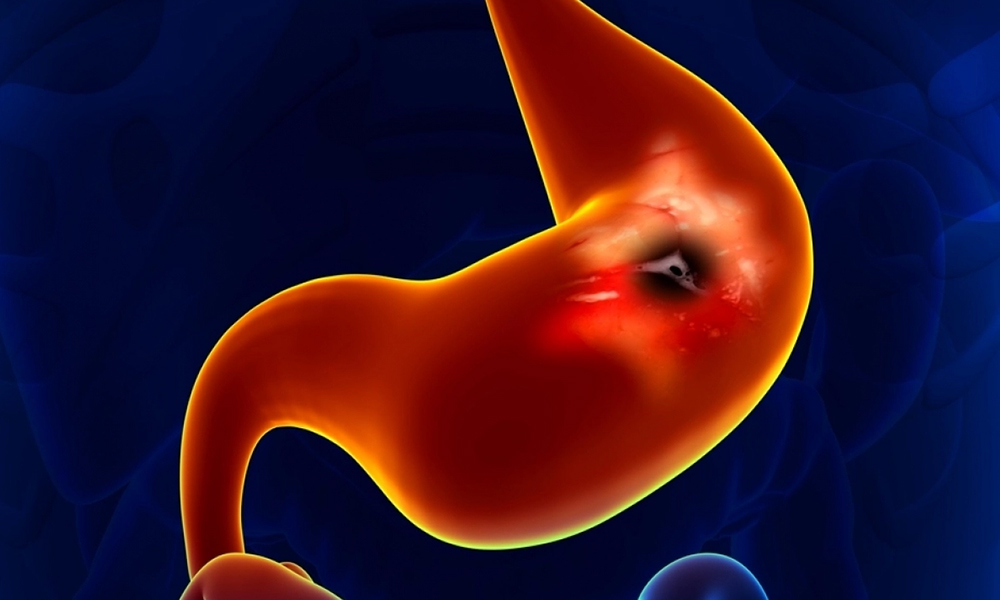

Gastric cancer surgery is a procedure performed to treat gastric cancer. When cancer cells grow in the lining of the stomach, a condition known as gastric cancer can result. Gastric cancer is also known as stomach cancer.The goal of gastric cancer surgery is to remove the cancerous tissue and surrounding lymph nodes. The type of surgery performed depends on the stage and location of the cancer, as well as the patient’s overall health.

Gastric cancer is one of the leading causes of cancer-related deaths worldwide. However, with early diagnosis and proper treatment, many patients are able to achieve a good outcome. Treatment options for gastric cancer typically include surgery, chemotherapy, and radiation therapy, and the type of treatment recommended will depend on the stage and location of the cancer, as well as the patient’s overall health.